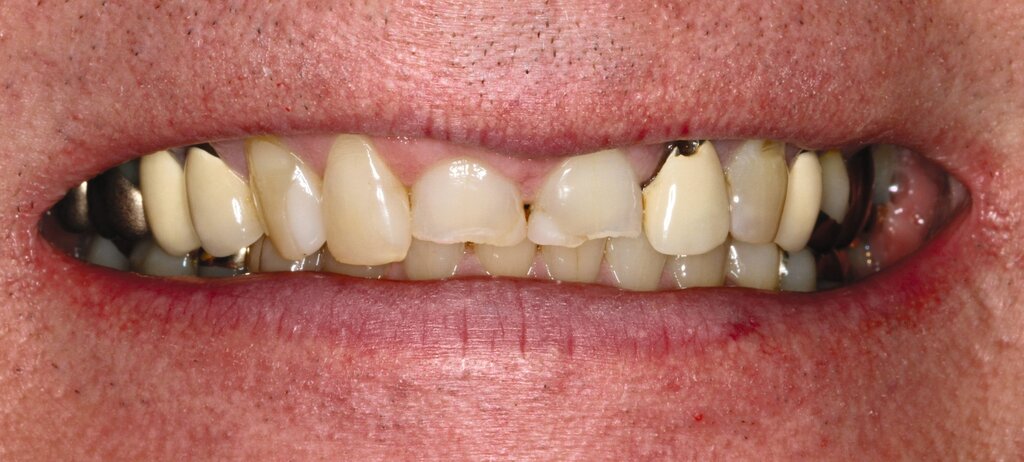

Die dentale Ausgangssituation zeigte im Seitenzahnbereich ein suffizient konservierend und prothetisch versorgtes Gebiss der zweiten Dentition sowie im Frontzahnbereich nicht kariogene Zahnhartsubstanzverluste und eine defekte Krone mit Sekundärkaries (Abbildungen 1 und 2).

Zur Verbesserung der Ästhetik und des Wohlbefindens des Patienten standen die Harmonisierung der Lachlinie und des Frontzahnbogens sowie Farb- und Formkorrekturen der Oberkieferfrontzähne im Fokus. An den Zähnen 11 und 21 waren Zahnhartsubstanzverluste durch Erosion und Attrition zu erkennen. Zahn 23 hatte ebenfalls einen erosiven Defekt, Zahn 13 eine farblich abweichende Kompositrestauration und die Zähne 14 und 24 wiesen keilförmige Defekte zervikal der Kronenränder auf, die einen suffizienten Randschluss haben (Abbildung 1a).

Vor 25 Jahren hatte der Patient ein Frontzahntrauma an Zahn 22 erlitten, der daraufhin mit einer Wurzelspitzenresektion und einer retrograden Amalgamfüllung versorgt worden war (Abbildung 3a). Dabei war die Zahnkrone mit einer keramisch verblendeten Stiftkrone aus Nichtedelmetall rekonstruiert worden, die nun aufgrund von Sekundärkaries insuffizient und gelockert war, jedoch keine Beschwerden verursachte. Klinisch wies der Zahn eine sehr kurze klinische Krone ohne ausreichendes Ferruledesign auf (Abbildung 5a) [Naumann et al., 2018a; Naumann et al., 2018b]. Neben dem Verdacht auf einen obliterierten mittleren Wurzelkanalabschnitt gab es röntgenologisch keinen Hinweis auf apikale Osteolysen oder parodontale Auffälligkeiten (Abbildung 3b). Der Patient entschied sich trotz des erhöhten Zahnhartsubstanzdefekts für den Zahnerhalt durch einen adhäsiv verankerten Kompositaufbau.

Die Zähne 11, 21 und 32–42 wiesen aufgrund des Zahnverschleißes stark verkürzte klinische Kronen auf. Durch diese Zahnhartsubstanzverluste sind die genannten Zähne über die Zeit elongiert – gut erkennbar an dem in Richtung Okklusionsebene verschobenen Verlauf des Gingivalsaums –, wodurch sich ein frontaler Tiefbiss und in Protrusion eine verzahnte Frontzahnführung im Schlüssel-Schloss-Prinzip mit veränderter Rot-Weiß-Ästhetik adaptiert haben. Daraus resultiert ein verringertes Platzangebot in statischer und in dynamischer Okklusion (Abbildungen 1b und 1d).